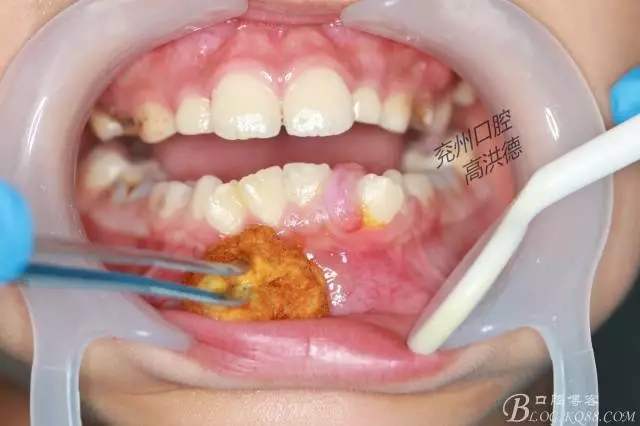

切除物